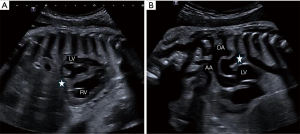

The second case involved a full-term male neonate. Routine prenatal screening, including fetal cardiac ultrasound at 12 and 22 weeks, was normal. The mother, aged 28 years, has not been exposed to NSAIDs or to other potential risk factors during pregnancy and has no significant medical history V体育平台登录. At 40 weeks of gestation +1/7, fetal echocardiography was performed due to cardiac rhythm abnormalities. Spontaneous premature closure of the DA was strongly suspected as it was impossible to demonstrate colored flow indicating patency of the DA (Figure 3). Other abnormalities were observed, including mild pericardial effusion, marked RV hypertrophy and dilatation, and moderate RV systolic dysfunction. The tricuspid valve was also dysplastic and showed mild regurgitation.

Premature DA occlusion was diagnosed before birth in only one of our two cases, using the standard sagittal view of the ductal arch view, which normally includes the DA in continuity with the main pulmonary trunk and descending aorta. In this case, color and pulsed Doppler echocardiography revealed absence of flow through the DA. Additional echocardiography findings included RV hypertrophy and dilatation, as well as dysplasia and varying degrees of regurgitation of both tricuspid and pulmonary valves.